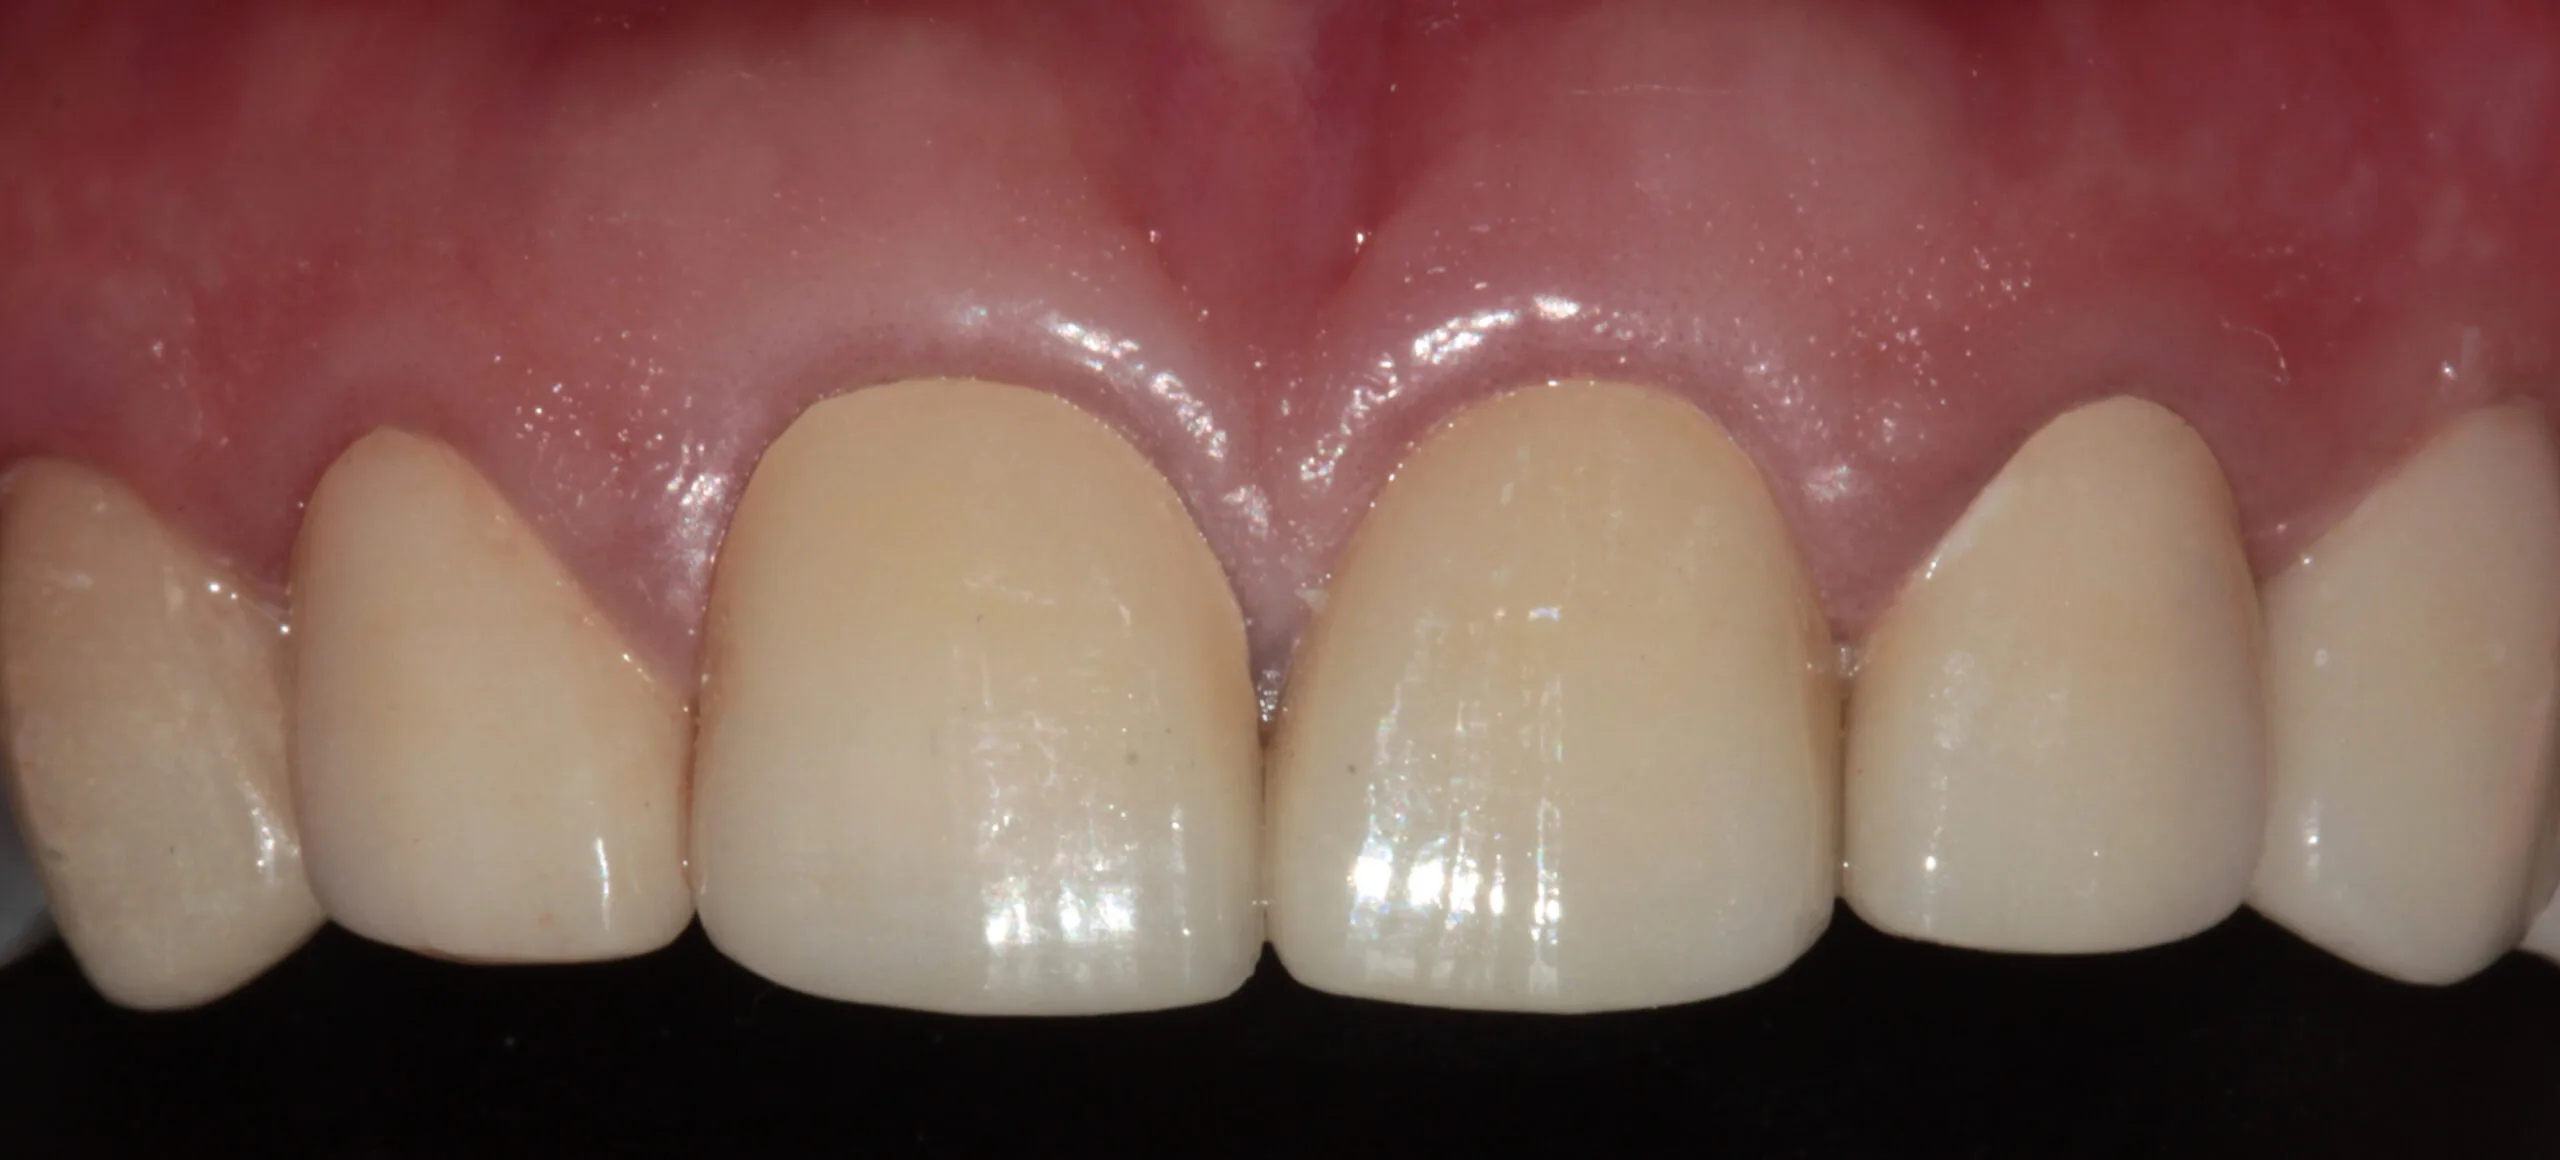

Cosmetic Dentistry